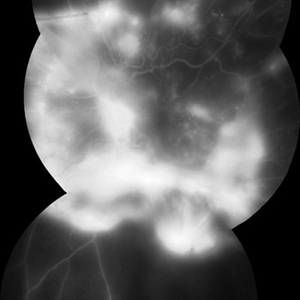

Photo of Large Hemorrhage with macular detachment due to AMD

Nov 7 2019 by John S. King, MD

81-year-old white female with three day history of seeing a "dark blob" nasally OD; no blood thinners; vision was 20/100- J16 with 2+NSC OD; OCT (not shown) had large SRF that included the fovea and extended out temporally. Posterior segment showed a large amount of SRF in the macula with some SRH in the inferior portion of the macula, hemorrhagic PEDs temporally with some RPE scarring and SRH in the periphery. On the FA there is blockage by the SRH and SRPE heme; there is staining peripherally; there is a wavbe of leakage that extends out into the macula and pools into to subretinal space. Anti-VEGF given; f/u one month.

Photographer: Brandon Peter

Condition/keywords: retinal pigment epithelium, subretinal hemorrhage, wet age-related macular degeneration (wet AMD)

FA 5 min - Large Hemorrhage With Macular Detachment Due to AMD

81-year-old white female with three day history of seeing a "dark blob" nasally OD; no blood thinners; vision was 20/100- J16 with 2+NSC OD; OCT (not shown) had large SRF that included the fovea and extended out temporally. Posterior segment showed a large amount of SRF in the macula with some SRH in the inferior portion of the macula, hemorrhagic PEDs temporally with some RPE scarring and SRH in the periphery. On the FA there is blockage by the SRH and SRPE heme; there is staining peripherally; there is a wavbe of leakage that extends out into the macula and pools into to subretinal space.

FA 40 Seconds - Large Hemorrhage With Macular Detachment Due to AMD

81-year-old white female with three day history of seeing a "dark blob" nasally OD; no blood thinners; vision was 20/100- J16 with 2+NSC OD; OCT (not shown) had large SRF that included the fovea and extended out temporally. Posterior segment showed a large amount of SRF in the macula with some SRH in the inferior portion of the macula, hemorrhagic PEDs temporally with some RPE scarring and SRH in the periphery. On the FA there is blockage by the SRH and SRPE heme; there is staining peripherally; there is a wave of leakage that extends out into the macula and pools into to subretinal space.